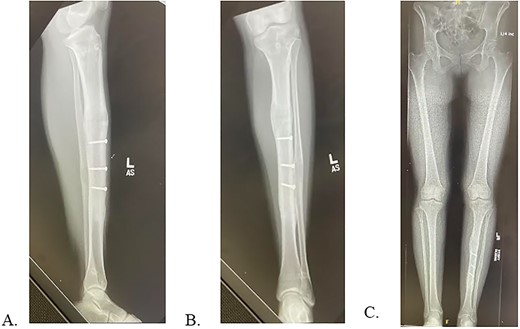

Final radiographs showed adequate alignment, internal fixation of the tibial osteotomy, and complete hardware removal aside from the three new fixation screws (Fig. 4A). The incisions were closed, dressed and the leg was immobilized in a Controlled Ankle Motion (CAM) boot. The patient spent six weeks non-weight bearing but was able to return to work without any pain or limping at three months post implant removal (Fig. 4B). Final 12-months follow-up demonstrated radiographically healed osteotomy site and maintained equal limb lengths and alignment (Fig. 5A-C).

A: Intraoperative radiograph demonstrating complete implant removal with x3 fixation screws. B: 6 weeks postoperative radiographs demonstrating maintained alignment at osteotomy site.

A: 12 months postoperative PRECICE explantation with osseous union at osteotomy site of lateral left tibia. B: 12 months postoperative PRECICE explantation with osseous union at osteotomy site of AP left tibia. C: 12 months postoperative PRECICE explantation with equal limb lengths and alignment.